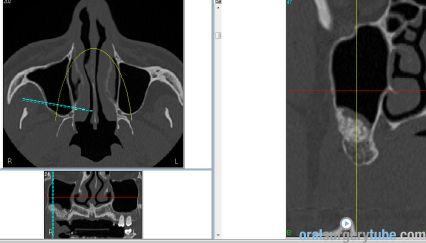

Con este comentario haremos una pausa en el caso hasta que llegue la colocación de los implantes. Por el momento, está todo solucionado. No hay sintomatología alguna, y lo más importante, en TAC realizado el martes 31.07.2018, podemos ver que el seno ha drenado por completo y está aireado. Hasta nuevo aviso, suspendemos todo tipo de medicación. Subimos imágenes del último TAC donde podemos apreciar que hemos perdido algo de xenoinjerto, pero la zona de menor altura aún tiene 10 mm. Podemos ver en una de las imágenes la zona de la ventana por donde el seno drenaba. Esperaremos el tiempo reglamentario para poder reevaluar si el xenoinjerto sigue siendo viable. Ha sido un gran placer contar con este equipo y poder aportar un grano de arena a solucionar complicaciones quirúrgicas.

Continúo con el seguimiento que vamos dando a este paciente: Visitado el miércoles 11.07.2018. Hay ausencia total de sintmatología. Retiramos el drenaje, hacemos Prueba de Valsalva positiva, pero sale aire y un poco de sangre. Dejamos cicatrizar por segunda intención. Pedimos continuar la medicación antibiótica y solicitamos un TAC. El seno maxilar está ocupado como vemos en la imagen, pero el biomaterial está contenido en la zona injertada: no existe ningún gránulo de xenoinjerto dentro del seno. La apófisis mastoidea está aireada.